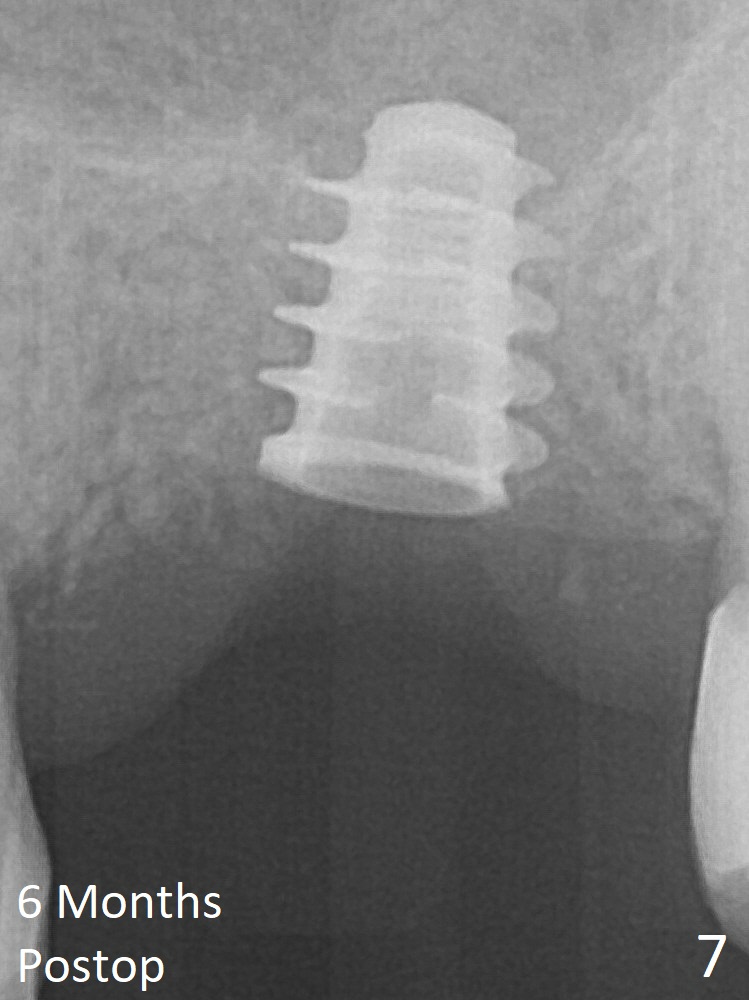

The implant is mobile 4 months postop (Fig.6). A 6x2 mm healing abutment is placed. Although the implant remains mobile 6 months postop, the bone seems to have become denser around the implant (Fig.7-9). A healing screw is placed.